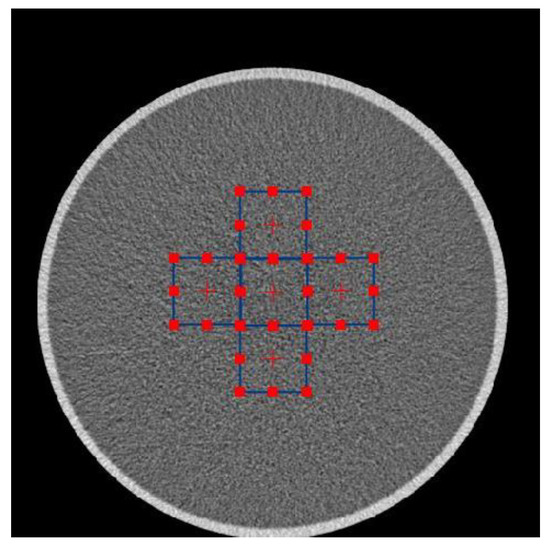

2.3. Implementation of Bilateral Filter, Measurement of Noise Power Spectrum and Spatial Resolution

2.4. Implementation of Anthropomorphic Phantom Images